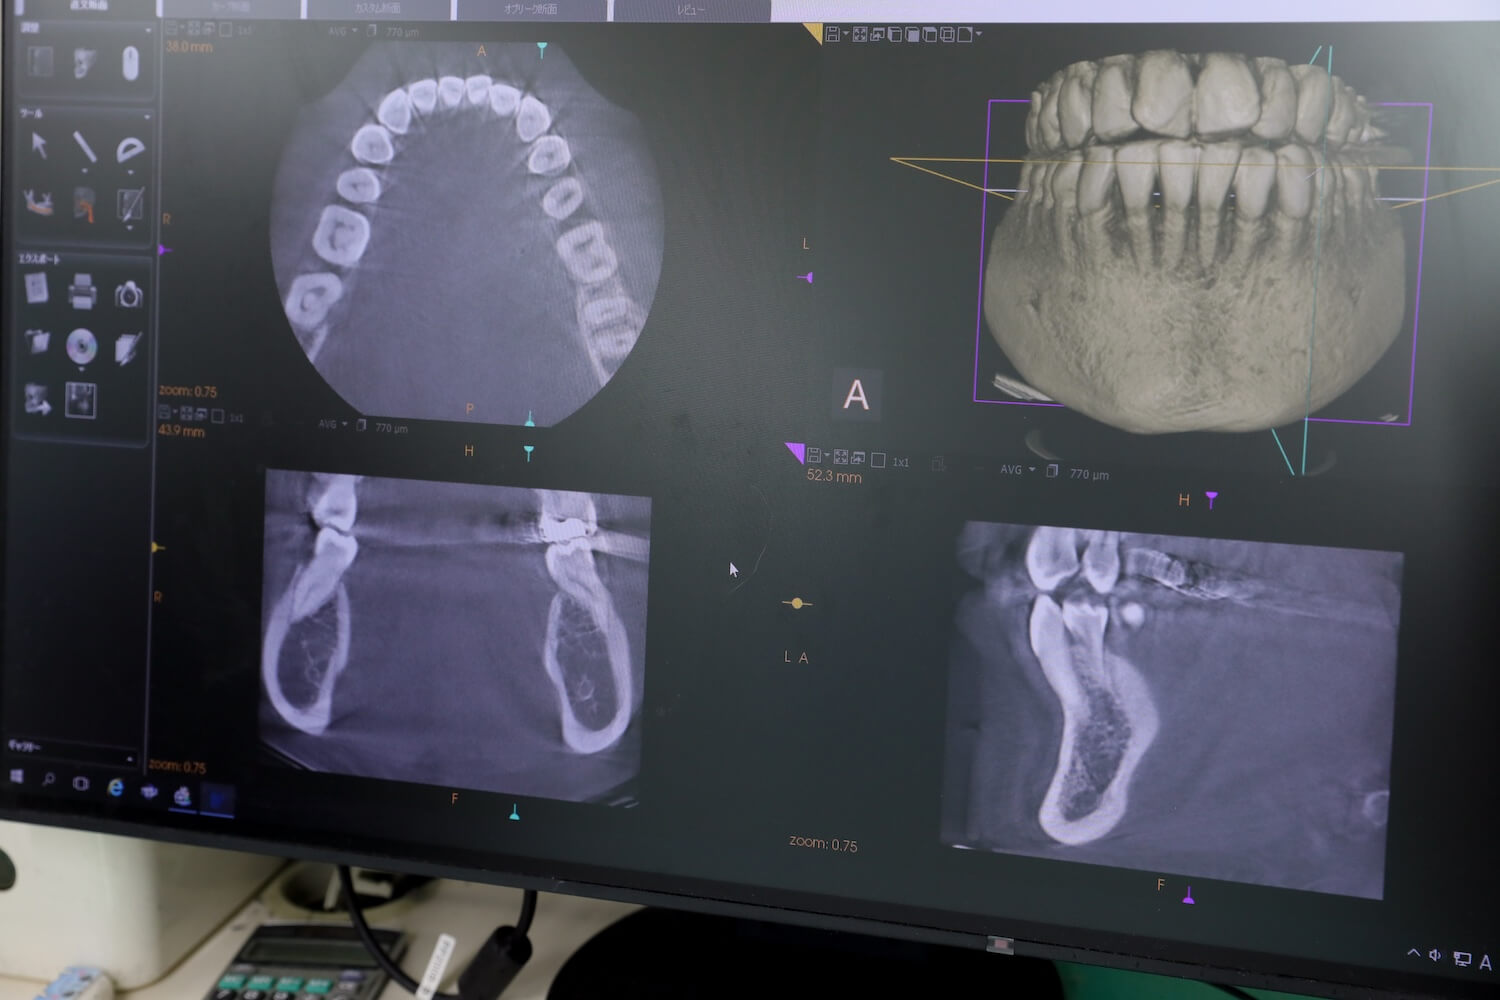

より安全性や確実性の高いインプラント治療を行うため、当院では歯科用CTを導入しています。従来のレントゲンでは2次元(平面)の情報しか分からず、外科的手術が必要となるインプラント治療ではリスクがあるからです。

CT撮影を行うことで、神経までの距離や血管(動脈)の位置、骨密度や骨量などの骨の状態を、3次元(立体的な3D画像)で詳細に把握することができます。